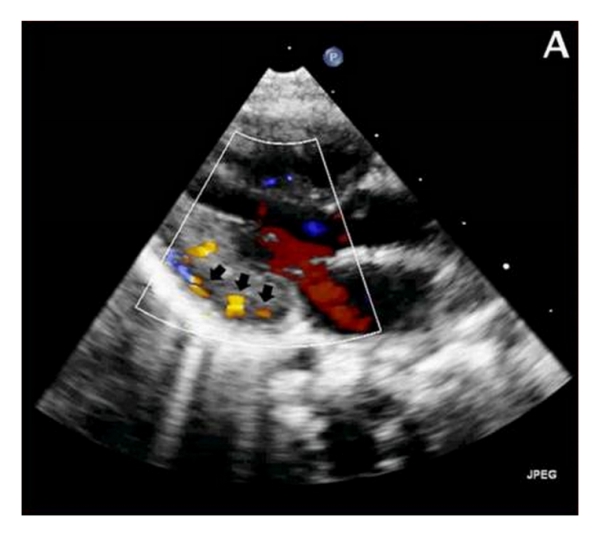

Regular pediatric follow-up at three months revealed a 3/6 systolic heart murmur. Subsequent echocardiography demonstrated multiple coronary artery microfistulas, originating from the left main coronary artery and draining into the left ventricle (Figure 1(a)). The latter was marginally hypertrophic but preserved normal contractility.

(a)

The left coronary artery was mildly dilated with an ostial diameter of 3.8 mm. Additionally, the patient manifested multiple small ventricular septal defects, as well as haemodynamically unsignificant patent ductus arteriosus and patent foramen ovale. The valves were normal. An angiogram performed at 4 months of age confirmed the above findings (Figure 1(b)).